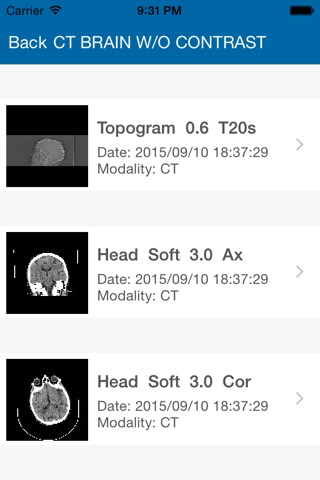

PHMI Mobile is an app for viewing x-ray studies performed at Peninsula Health. Peninsula Health is a leading provider of radiology services in the Frankston and Mornington Peninsula areas. Access to PHMI Mobile is for registered referrers only. Please contact Peninsula Health Medical Imaging Department if you are a referrer and wish to have access to radiology reports and images via PHMI Mobile.